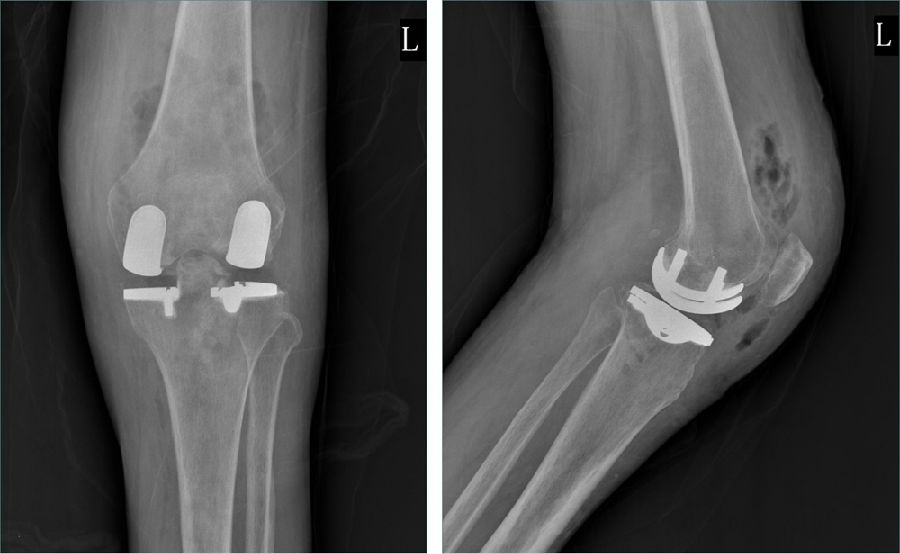

Case1LUK治疗外侧间室OA

术前

术后